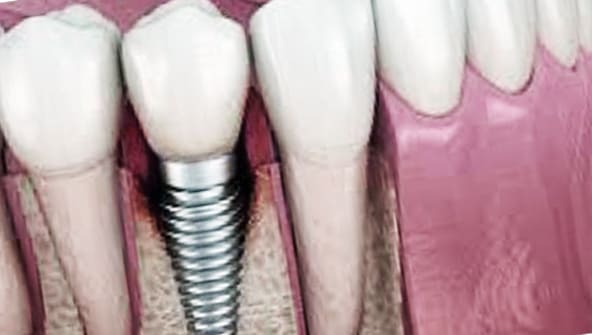

모든 종류의 치아 중에서 어금니는 씹는 데 매우 중요한 역할을 합니다. 그러나 많은 사람들이 어금니의 중요성을 무시하고 충치가 발생하면 조기 치료 없이 치료를 받지 못하는 경우가 많습니다. 어금니를 치료하지 않으면 시간이 지남에 따라 치아의 부식이 증가하여 치아 추출이 필요합니다. 어금니 이식은 어금니를 제거했을 때 받는 시술입니다.

이때 임플란트는 틀니와 달리 자연치와 비슷한 씹는 힘이 있고 잘 유지되면 장기간 사용할 수 있습니다.